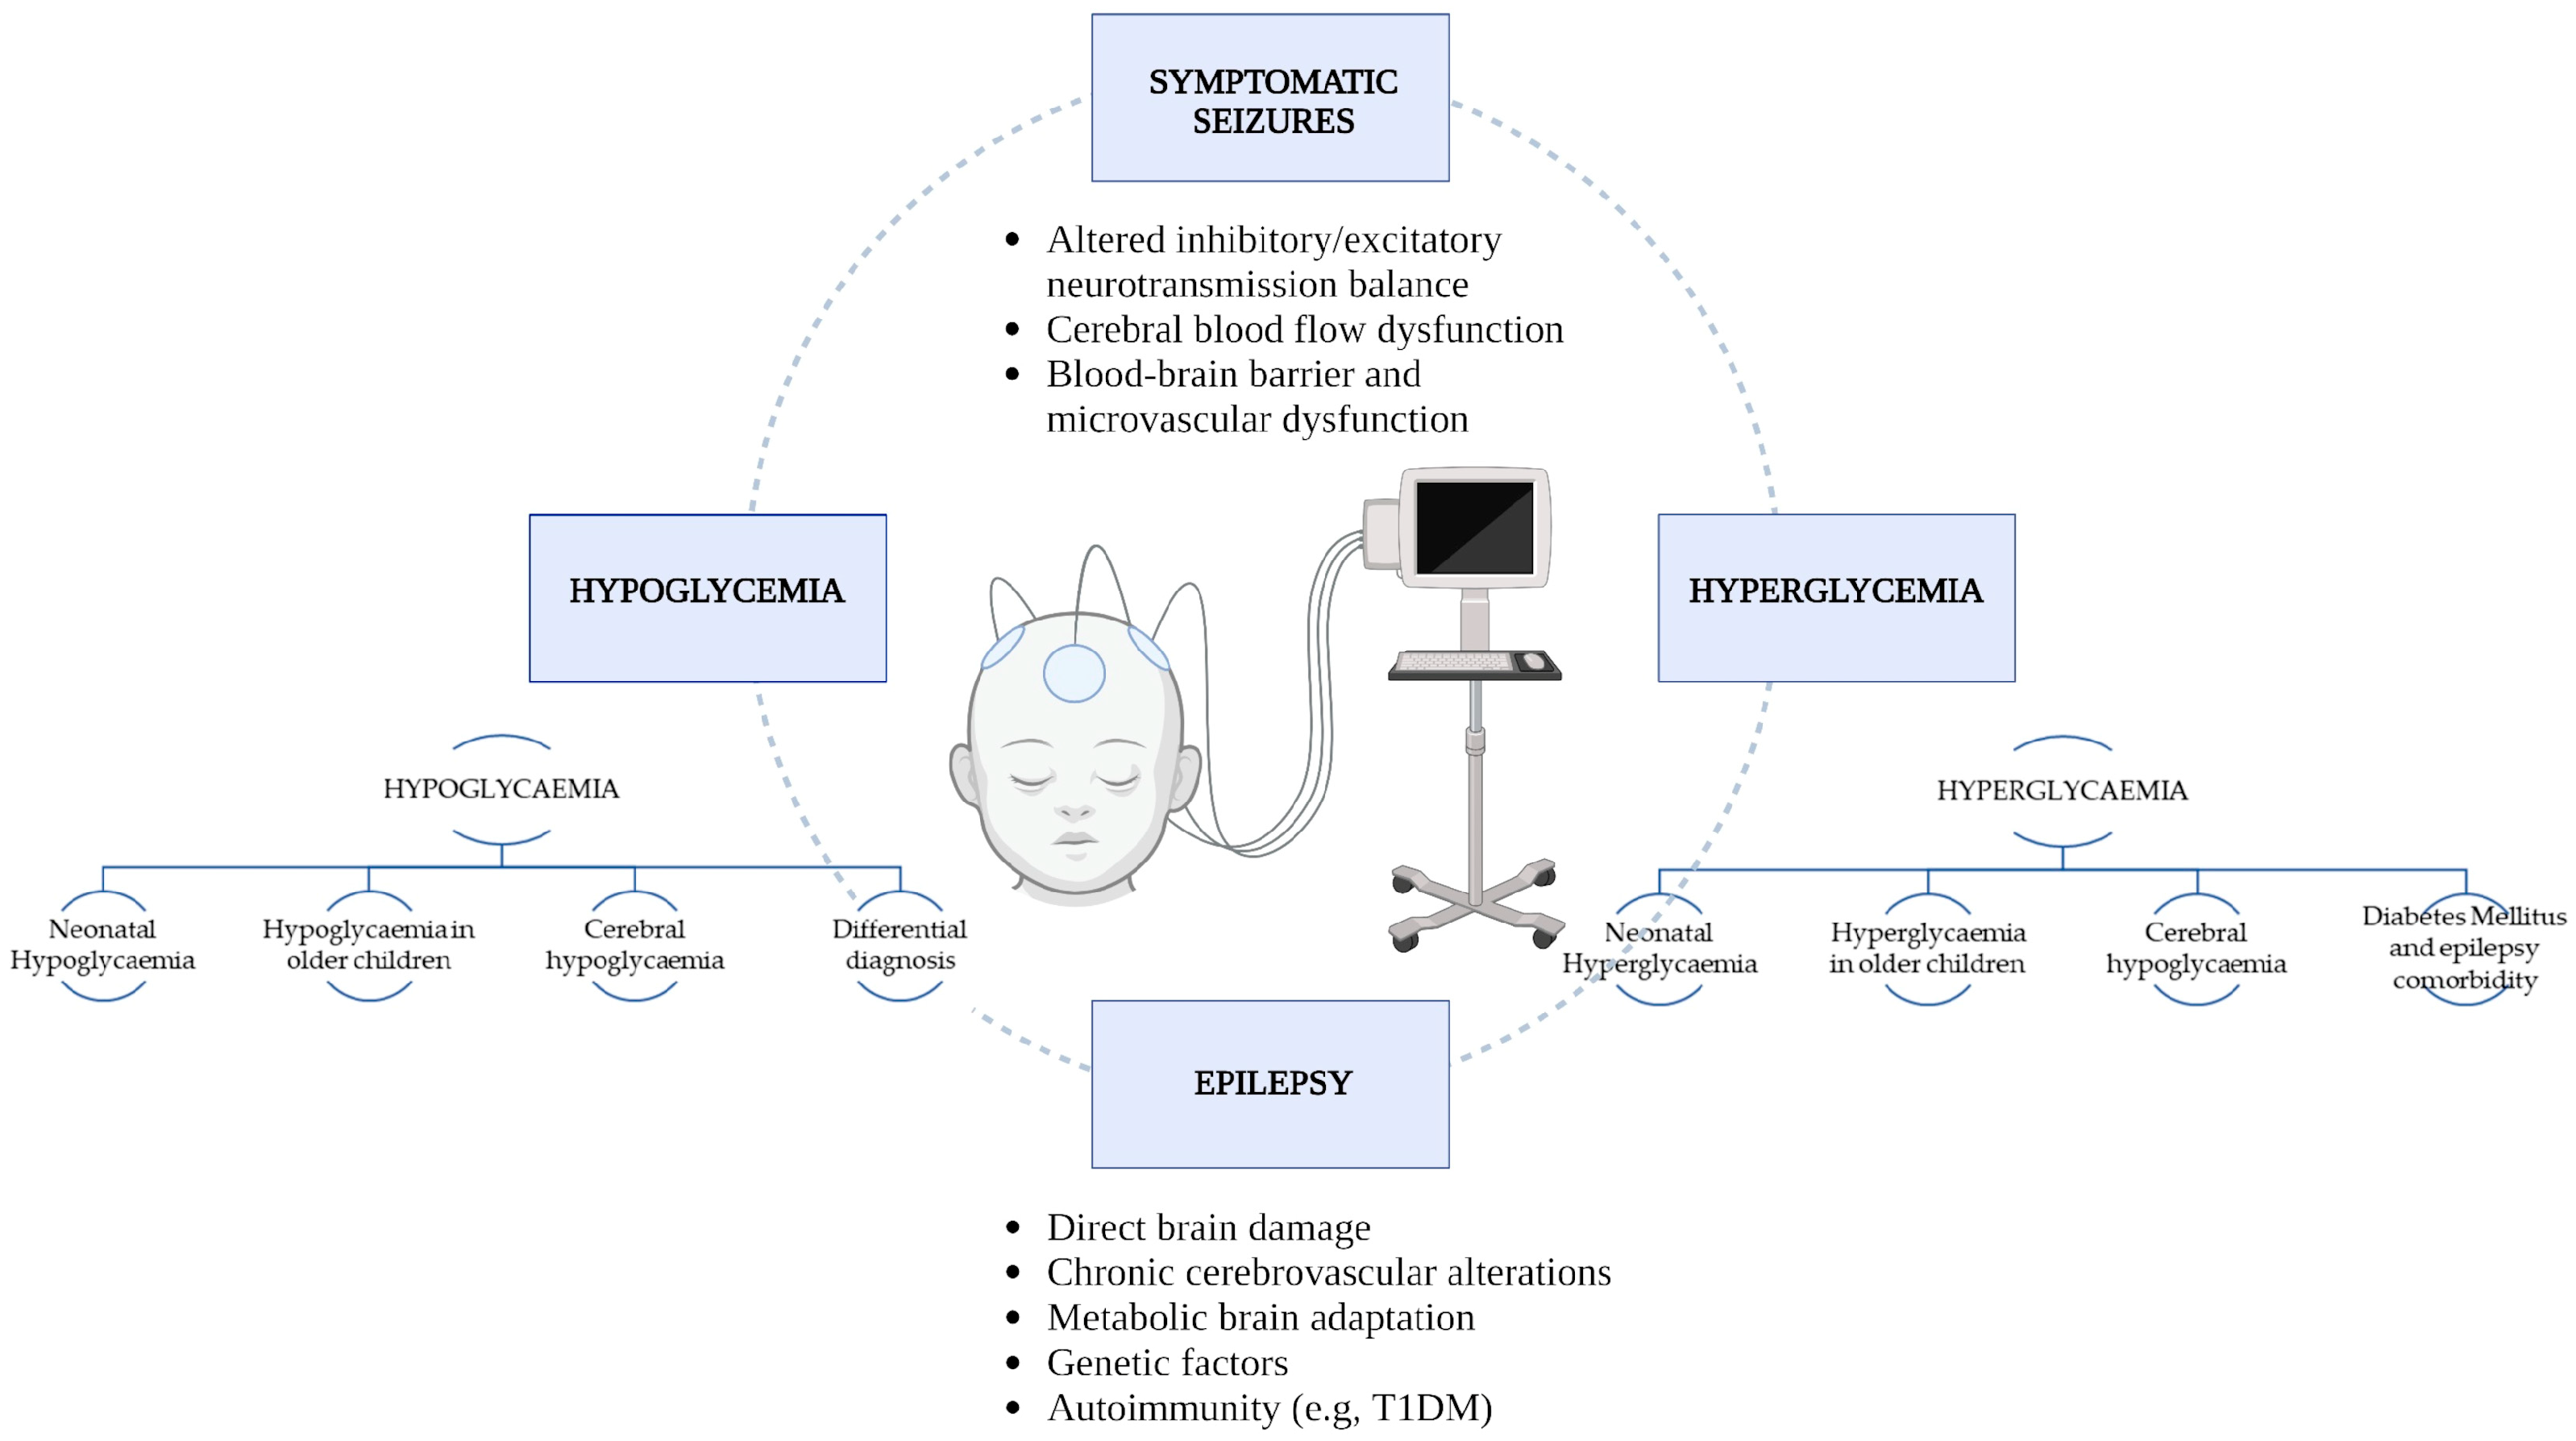

Glycaemic Imbalances in Seizures and Epilepsy of Paediatric Age: A Literature Review

Abstract

1. Introduction

3. Results

3.1. Hypoglycaemia

3.2. Hyperglycaemia

4. Conclusions